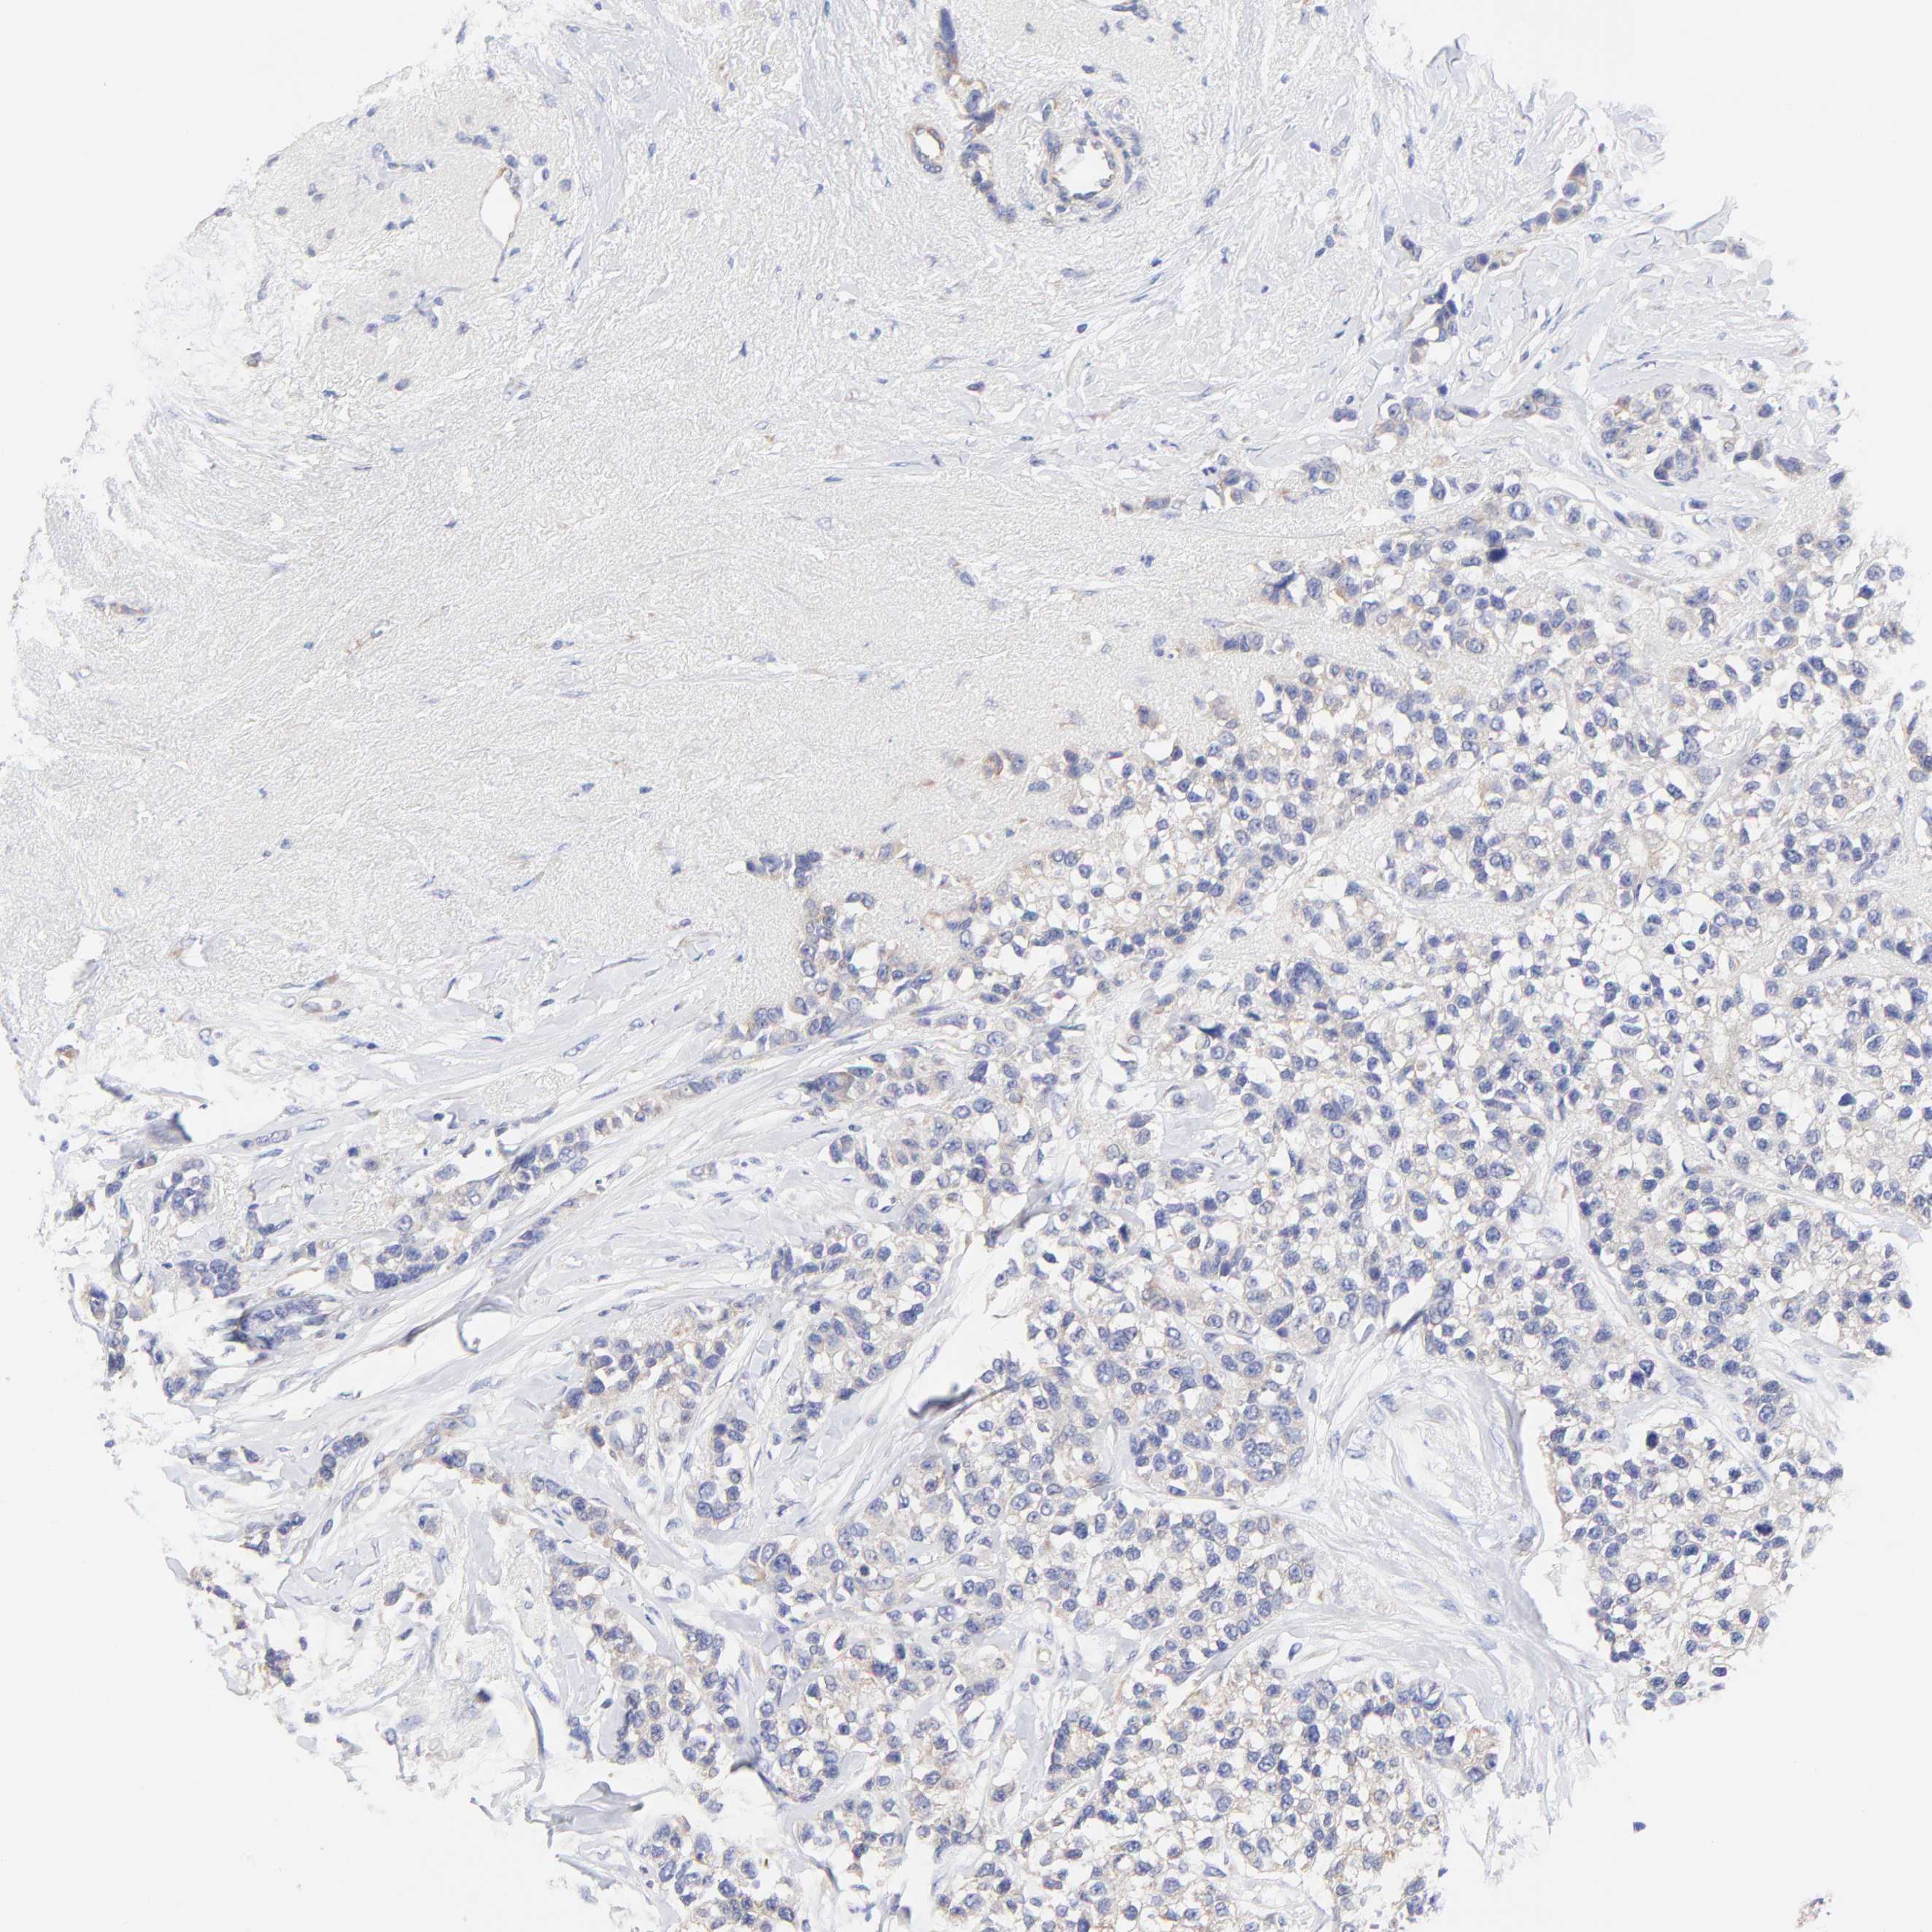

BRCA TCGA BRCA VALIDATION PROTEIN EXPRESSION

ANTIBODIES

AND

VALIDATION